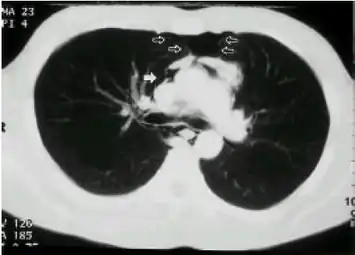

| A CT scan showing air in the mediastinum | |

Pneumomediastinum is uncommon and occurs when air leaks into the mediastinum. The diagnosis can be confirmed via chest X-ray showing a radiolucent outline around the heart and mediastinum or via CT scanning of the thorax.